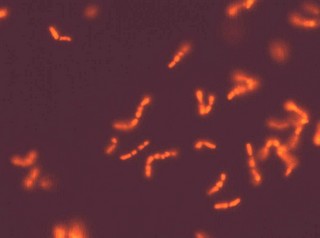

Some examples of FISH images

The detection of whole-bacterial cells via the labelling of specific nucleic acids with fluorescently labelled oligonucleotide probes is called fluorescence in situ hybridization (FISH)